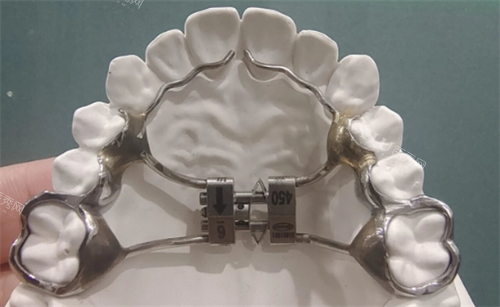

“孩子牙弓窄,牙齿挤得歪歪扭扭,扩弓器能矫正吗?”“我都30岁了,还能用扩弓器调整牙齿吗?”——这类问题在口腔正畸门诊里几乎天天被问到。今天咱们就掰开揉碎聊聊扩弓器的适用年龄,顺便揭开“成年人扩弓”的真相。

8-14岁是扩弓器矫正的“黄金窗口期”,尤其是12-13岁的替牙期尾声,堪称“黄金中的黄金”。为啥呢?因为这个阶段的孩子正处于颌骨快速发育期,牙槽骨就像一块“海绵”,在矫治器的牵引下更容易被重塑。

临床数据显示,8-14岁佩戴扩弓器的孩子,矫正周期平均比成人短30%-50%。比如12岁的小明,因为上颚骨缝未闭合,佩戴扩弓器3个月后牙弓宽度增加了4毫米,而30岁的成年人可能需要6个月甚至更久才能达到类似结果。不过,这个年龄段的孩子也有“小脾气”——比如需要定期复诊调整矫治器,初期可能因牙槽骨扩张产生轻微胀痛感,但这些通常在1周内缓解。

过了14岁,尤其是16岁以后,颌骨发育逐渐进入“平台期”。此时牙槽骨的“可塑性”降低,扩弓结果就像“在石头上刻字”,需要更强的矫治力,且更容易反弹。但并非完全“没救”,医生会根据牙弓狭窄程度、牙齿拥挤度等指标综合判断。比如,15岁的小丽因腭盖高拱导致前牙外突,通过佩戴改良型扩弓器配合固定矫治器,1年后牙弓宽度增加了3毫米,咬合关系显著改善。

“成年人扩弓就像在水泥地上种花”——这是口腔正畸圈的一句玩笑话,却道出了真相。30岁后,牙槽骨密度增加,矫治器需要施加更大的力量才能让牙弓“变宽”,但这种力量可能引发牙根吸收、牙周膜损伤等副作用。比如,28岁的张先生因牙齿拥挤选择扩弓,结果因矫治力过大导致2颗前牙牙根暴露,不得不暂停治疗。

不过,并非所有成年人都“无缘扩弓”。轻中度牙列拥挤、牙弓形态异常者,在排除牙周炎、颞下颌关节紊乱等禁忌症后,可在医生评估下尝试。但治疗周期可能延长至1-2年,且需长期佩戴保持器防止复发。

扩弓器矫正牙齿的较佳年龄虽在8-14岁之间,但方案需由靠谱正畸医生根据牙片、模型、面型等综合判断。无论是孩子还是成年人,扩弓治疗都像一场“马拉松”,需要耐心配合复诊、保持口腔卫生、避免硬物撞击矫治器